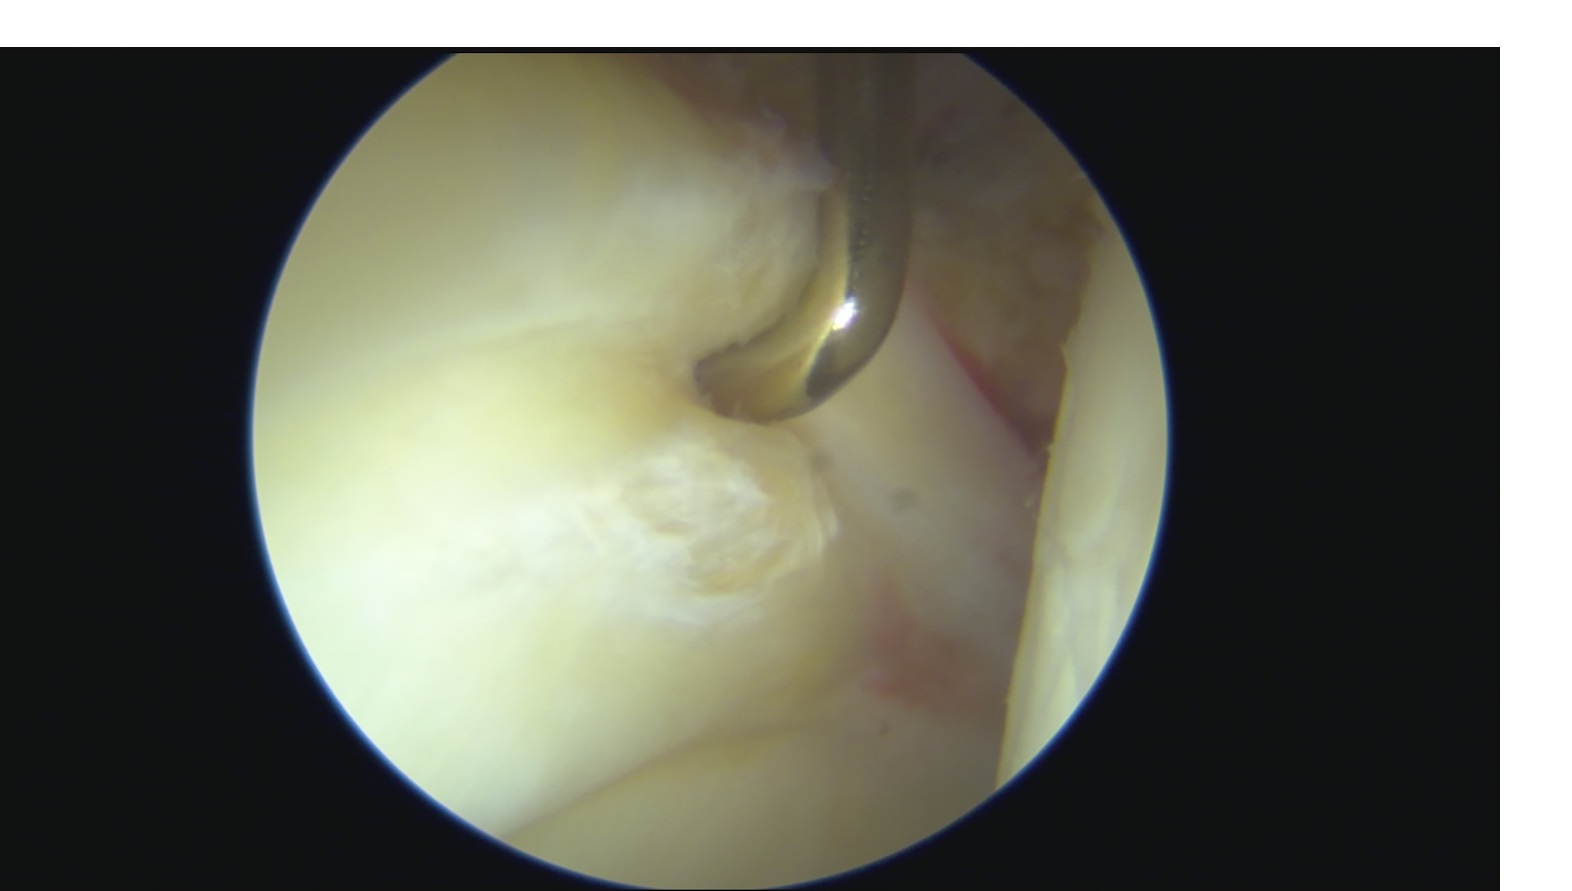

Il conflitto femoro-acetabolare comporta una lesione del labbro acetabolare

(Fig.2), che è una sorta di guarnizione dell’articolazione che riveste il bordo dell’acetabolo e che garantisce un effetto vacuum (seal effect), limitando così l’attrito articolare. In seguito alla lesione del labbro, si ha dolore e alterazione dell’omeostasi dei carichi articolari. Tale situazione comporta prima un danneggiamento localizzato della cartilagine acetabolare, e poi con il passare degli anni e il proseguimento dell’attivitè sportiva può anche condurre ad un’artrosi conclamata.

- Danno iniziale con lesione del labbro acetabolare: artroscopia dell’anca con riparazione del labbro acetabolare (Fig.3)